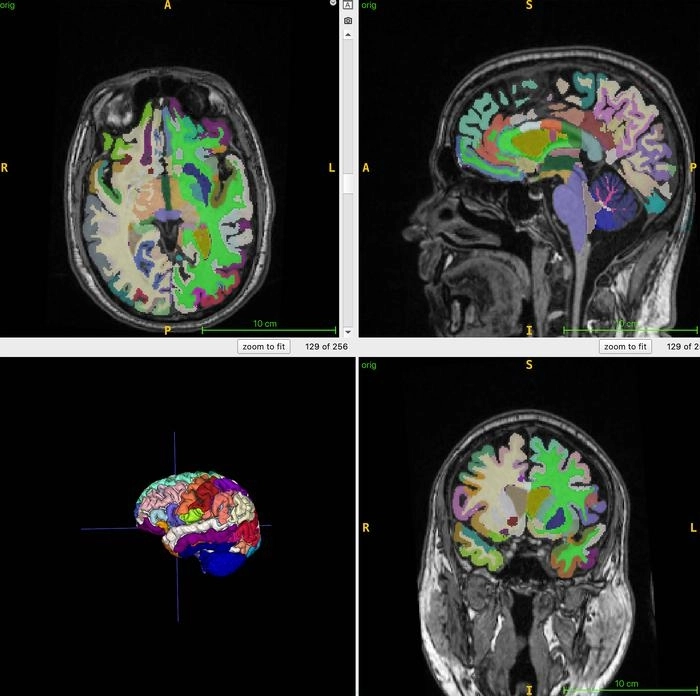

연구팀은 건강한 성인 남녀 1164명을 대상으로 전신 MRI 검사를 했다. 연구팀은 지방은 밝게, 액체는 어둡게 보여줘 근육, 지방, 뇌 조직을 최적으로 영상화할 수 있게 하는 T1 강조 영상 기법을 결합했다.

연구팀은 MRI-T1 영상을 인공지능 알고리즘을 사용해 전체 근육량, 내장 지방, 피하 지방, 뇌 나이를 정량화했다.